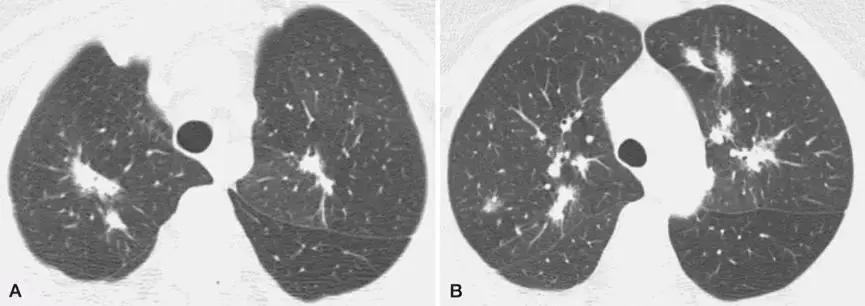

2、影像学是诊断线索

OP的影像表现:实变(周围、沿支气管血管束):80~95%;磨玻璃影:60~90%;小叶间隔增厚:55%;「反晕征」:20%;结节或团块:15~50%;还有「游走性」的特点。

实变:

中心型

混合型

磨玻璃影:

GGO合并带状实变

GGO,合并周围型及带状实变

小叶间隔增厚:

小叶间隔增厚,伴中心型实变、GGO

反晕征:

结节或团块(需要和肿瘤鉴别):